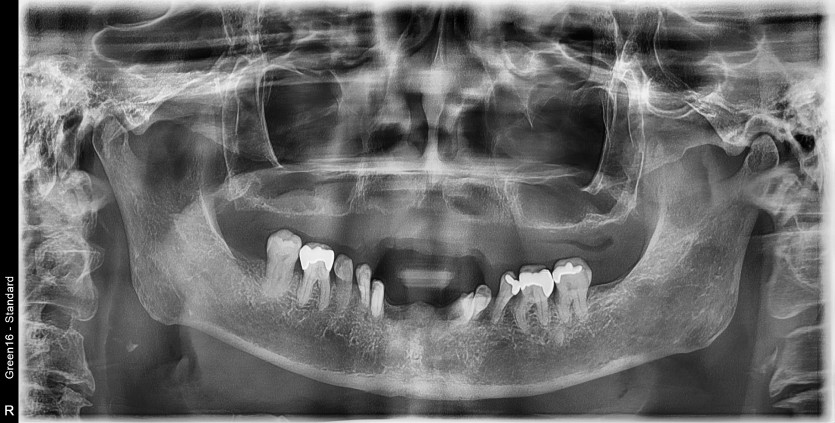

만 68세 하악 전체 임플란트 증례(상악 기존틀니 사용)

하악 전체 임플란트 증례입니다.

(상악 기존틀니 사용)

8개의 임플란트로 완성하였습니다.